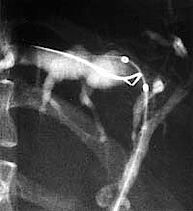

Die Ballondilatation wird bei der primär sklerosierenden Cholangitis (PSC) angewandt. Die PSC ist eine entzündliche Erkrankung der Gallenwege, die zu einem Nebeneinander von entzündlich- vernarbenden Engstellen einerseits und Gangerweiterungen andererseits führt [Abb. 1]. Durch die Engstellen im Gallengang kommt es zu einem Gallenaufstau mit Ikterus (Gelbsucht). Werden die Engstellen durch eine Ballondilatation aufgedehnt, kann ein ausreichender Gallefluss erreicht werden [Abb. 3]. Ballondilatationen von Engstellen der Gallengänge bei PSC wirken sich wahrscheinlich günstig auf das Fortschreiten der Erkrankung aus. Belegt wird dieses Vorgehen durch eine an der Universität Heidelberg durchgeführte Studie, die weltweite Anerkennung fand.